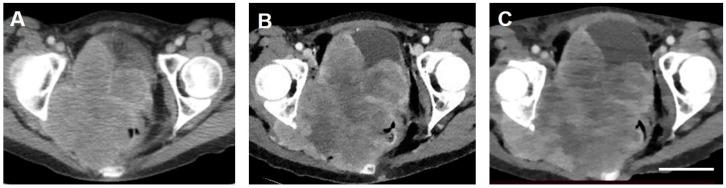

Emergency Use of Targeted Osmotic Lysis for the Treatment of a Patient with Aggressive Late-Stage Squamous Cell Carcinoma of the Cervix.

Upregulation of voltage-gated sodium channels (VGSCs) and Na/K-ATPase (sodium pumps) is common across most malignant carcinomas. Targeted osmotic lysis (TOL) is a developing technology in which the concomitant stimulation of VGSCs and pharmacological blockade of sodium pumps causes rapid selective osmotic lysis of carcinoma cells. This treatment of cervical carcinoma is evidence that TOL is a safe, well-tolerated and effective treatment for aggressive advanced carcinomas that has the potential to extend life without compromising its quality. TOL is likely to have broad application for the treatment of advanced-stage carcinomas.